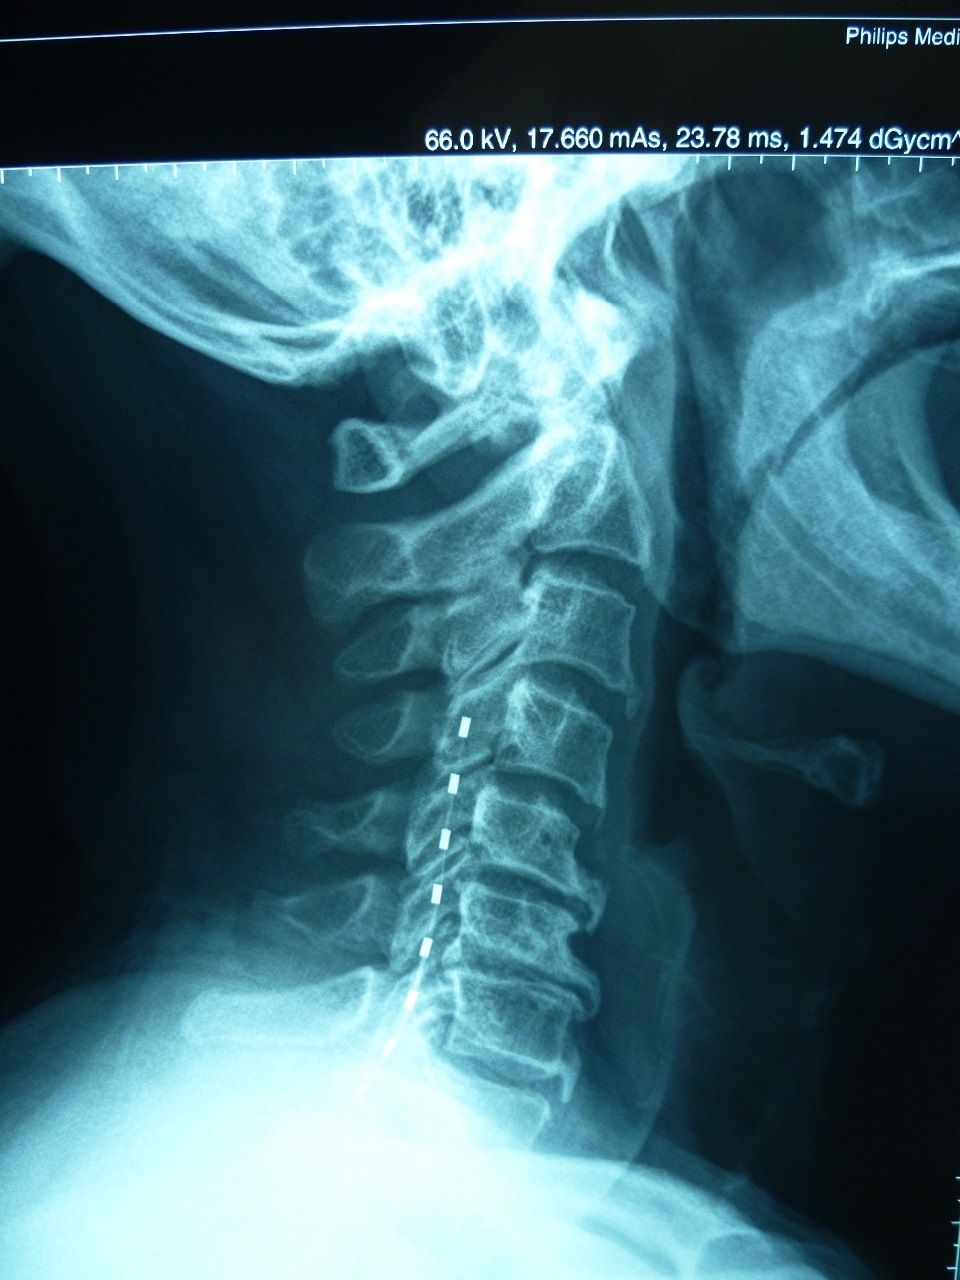

Electrodes placed in the cervical spine epidurally for the treatment of neuropathic pain.